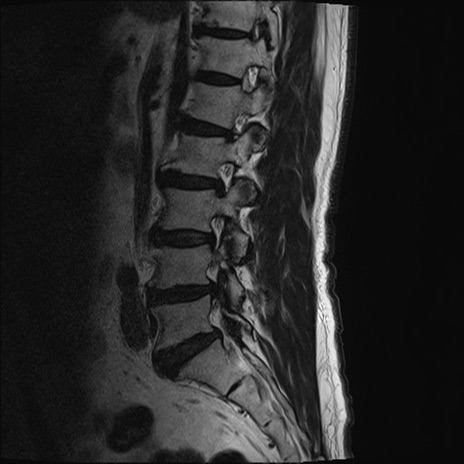

【整形】TIPS症例2 腰椎MRI T2WI(矢状断像)

【症例】70歳代男性

【主訴】左下肢痛

【現病歴】2週間前くらいから腰痛、左下肢痛あり。左臀部から大腿、下腿外側のしびれが常時ある。歩行とともに同部位の痛みあり。

【身体所見】Lasegue70-/60+、Bragard-/±、PTR ±/±、ATR -/-、IP 5/5、TA 5/4、TS 5/5、EHL 右第1足趾なし/3、FHL 5/5、hypersthesia(-)、足背動脈触知良好

異常所見と診断は?